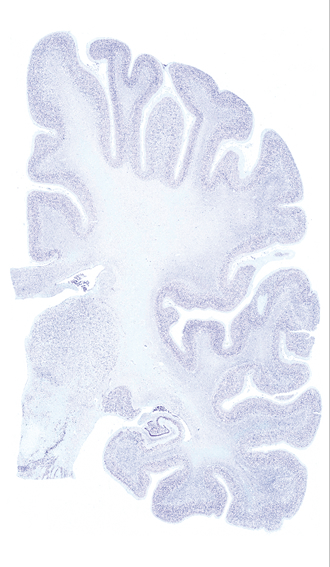

Hi-Resolution Sections · Cells (Nissl Staining) · Virtual Microscopy

Frontal sections (Nissl) from the Atlas Brain:

Microscopy

Slice ID:

r3-0405

Plate NR:

42

Position:

26,5 mm